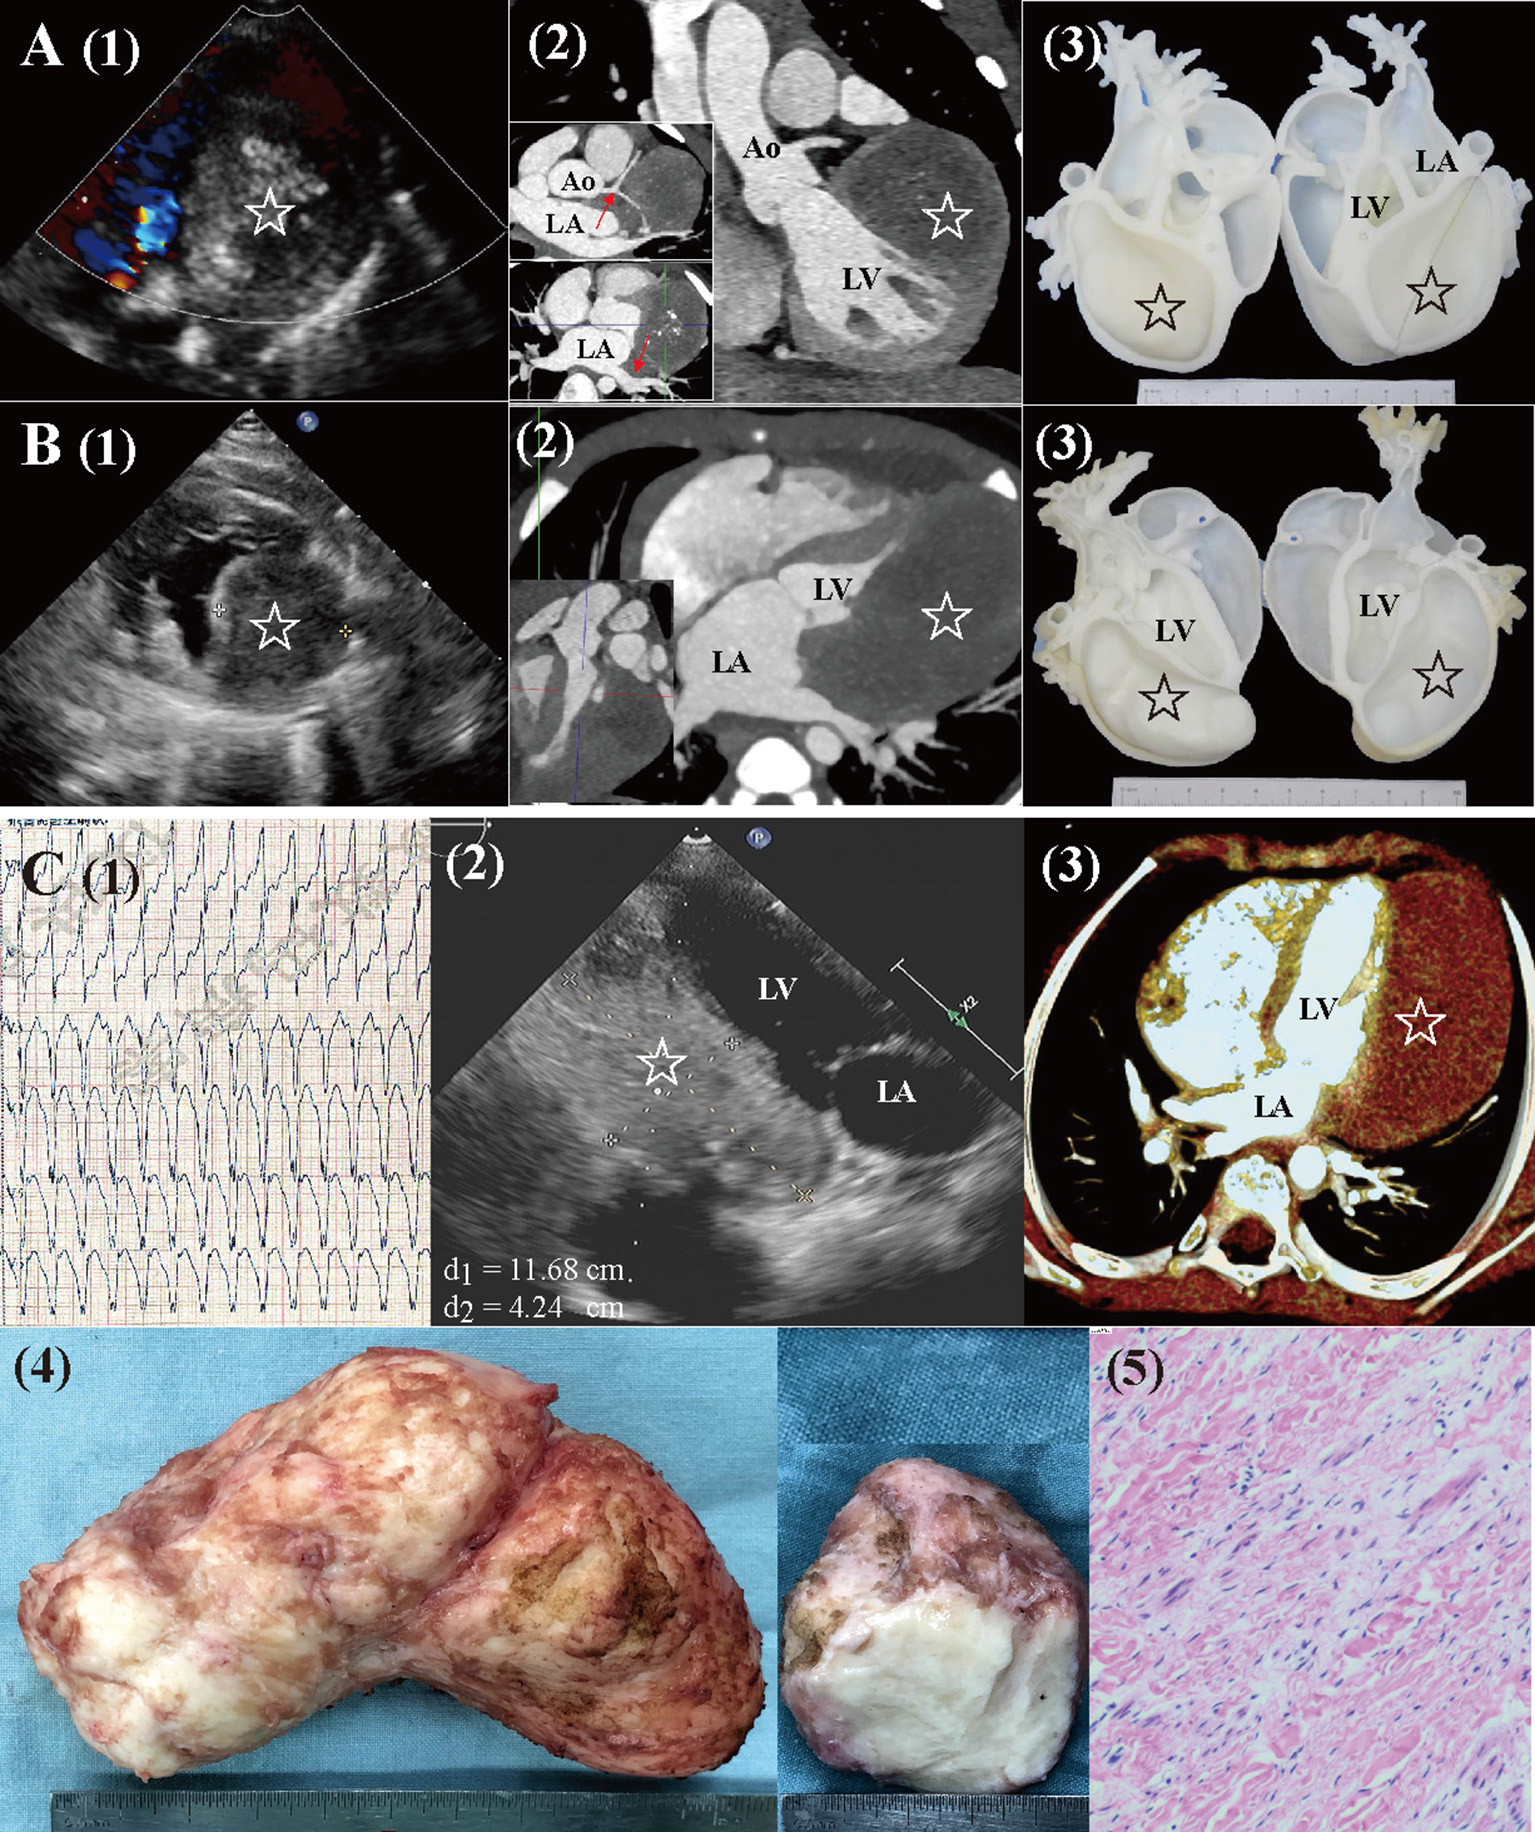

Magnetic resonance imaging and CTA were performed to evaluate the mass characteristics, cardiac function, and surrounding structures. Cardiac 3D-printed models were obtained for 2 patients with large fibromas to optimize surgical planning (Figures 1A,B).

Figure 1. Preoperative workups and surgical resection of large cardiac fibromas. (A) Echocardiography, CTA, and 3D-printed models for a 4.2-year-old female. The mass (star) extended close to the left coronary artery and left pulmonary veins [red arrow in (2)], with visible calcification. (B) Echocardiography, CTA, and 3D-printed models for a 6-month-old male. The mass (star) extended from the base to the apex, with a distinctly larger volume than that of LV. (C) A 7.5-year-old male (1) presented with sustained ventricular tachycardia (176 bpm). (2, 3) Echocardiography and CTA revealed a huge mass (star. length: 12 cm, volume: 213 ml, and volume index: 227 ml/m2) located at LV posterolateral wall. (4, 5) Gross specimen and histologic examination of the mass, typical of fibroma. Ao, aorta; CTA, computed tomography angiography; LA, left atria; LV, left ventricle.

The median length, volume, and volume index of fibromas were 52 mm (IQR: 38 to 56), 59 ml (IQR: 44 to 88), and 101 ml/m2 (IQR: 41 to 169; mean: 105 ± 70 ml/m2). The largest fibroma was shown in Figure 1C. There was no correlation between the length and volume of fibromas with age (Ps > 0.05, Figures 3A,B). The fibroma volume index was significantly negative corrected with age (P = 0.039. Figure 3C). The size of the fibromas was similar between symptomatic (n = 10) and asymptomatic (n = 5) patients (Ps > 0.05, Figures 3D–F). Symptomatic patients had similar age with asymptomatic patients (median: 4.2 vs. 6.5 years, P = 0.940). In total, 10 of the 15 (66.7%) patients had a larger fibroma volume index than the LVEDV index.